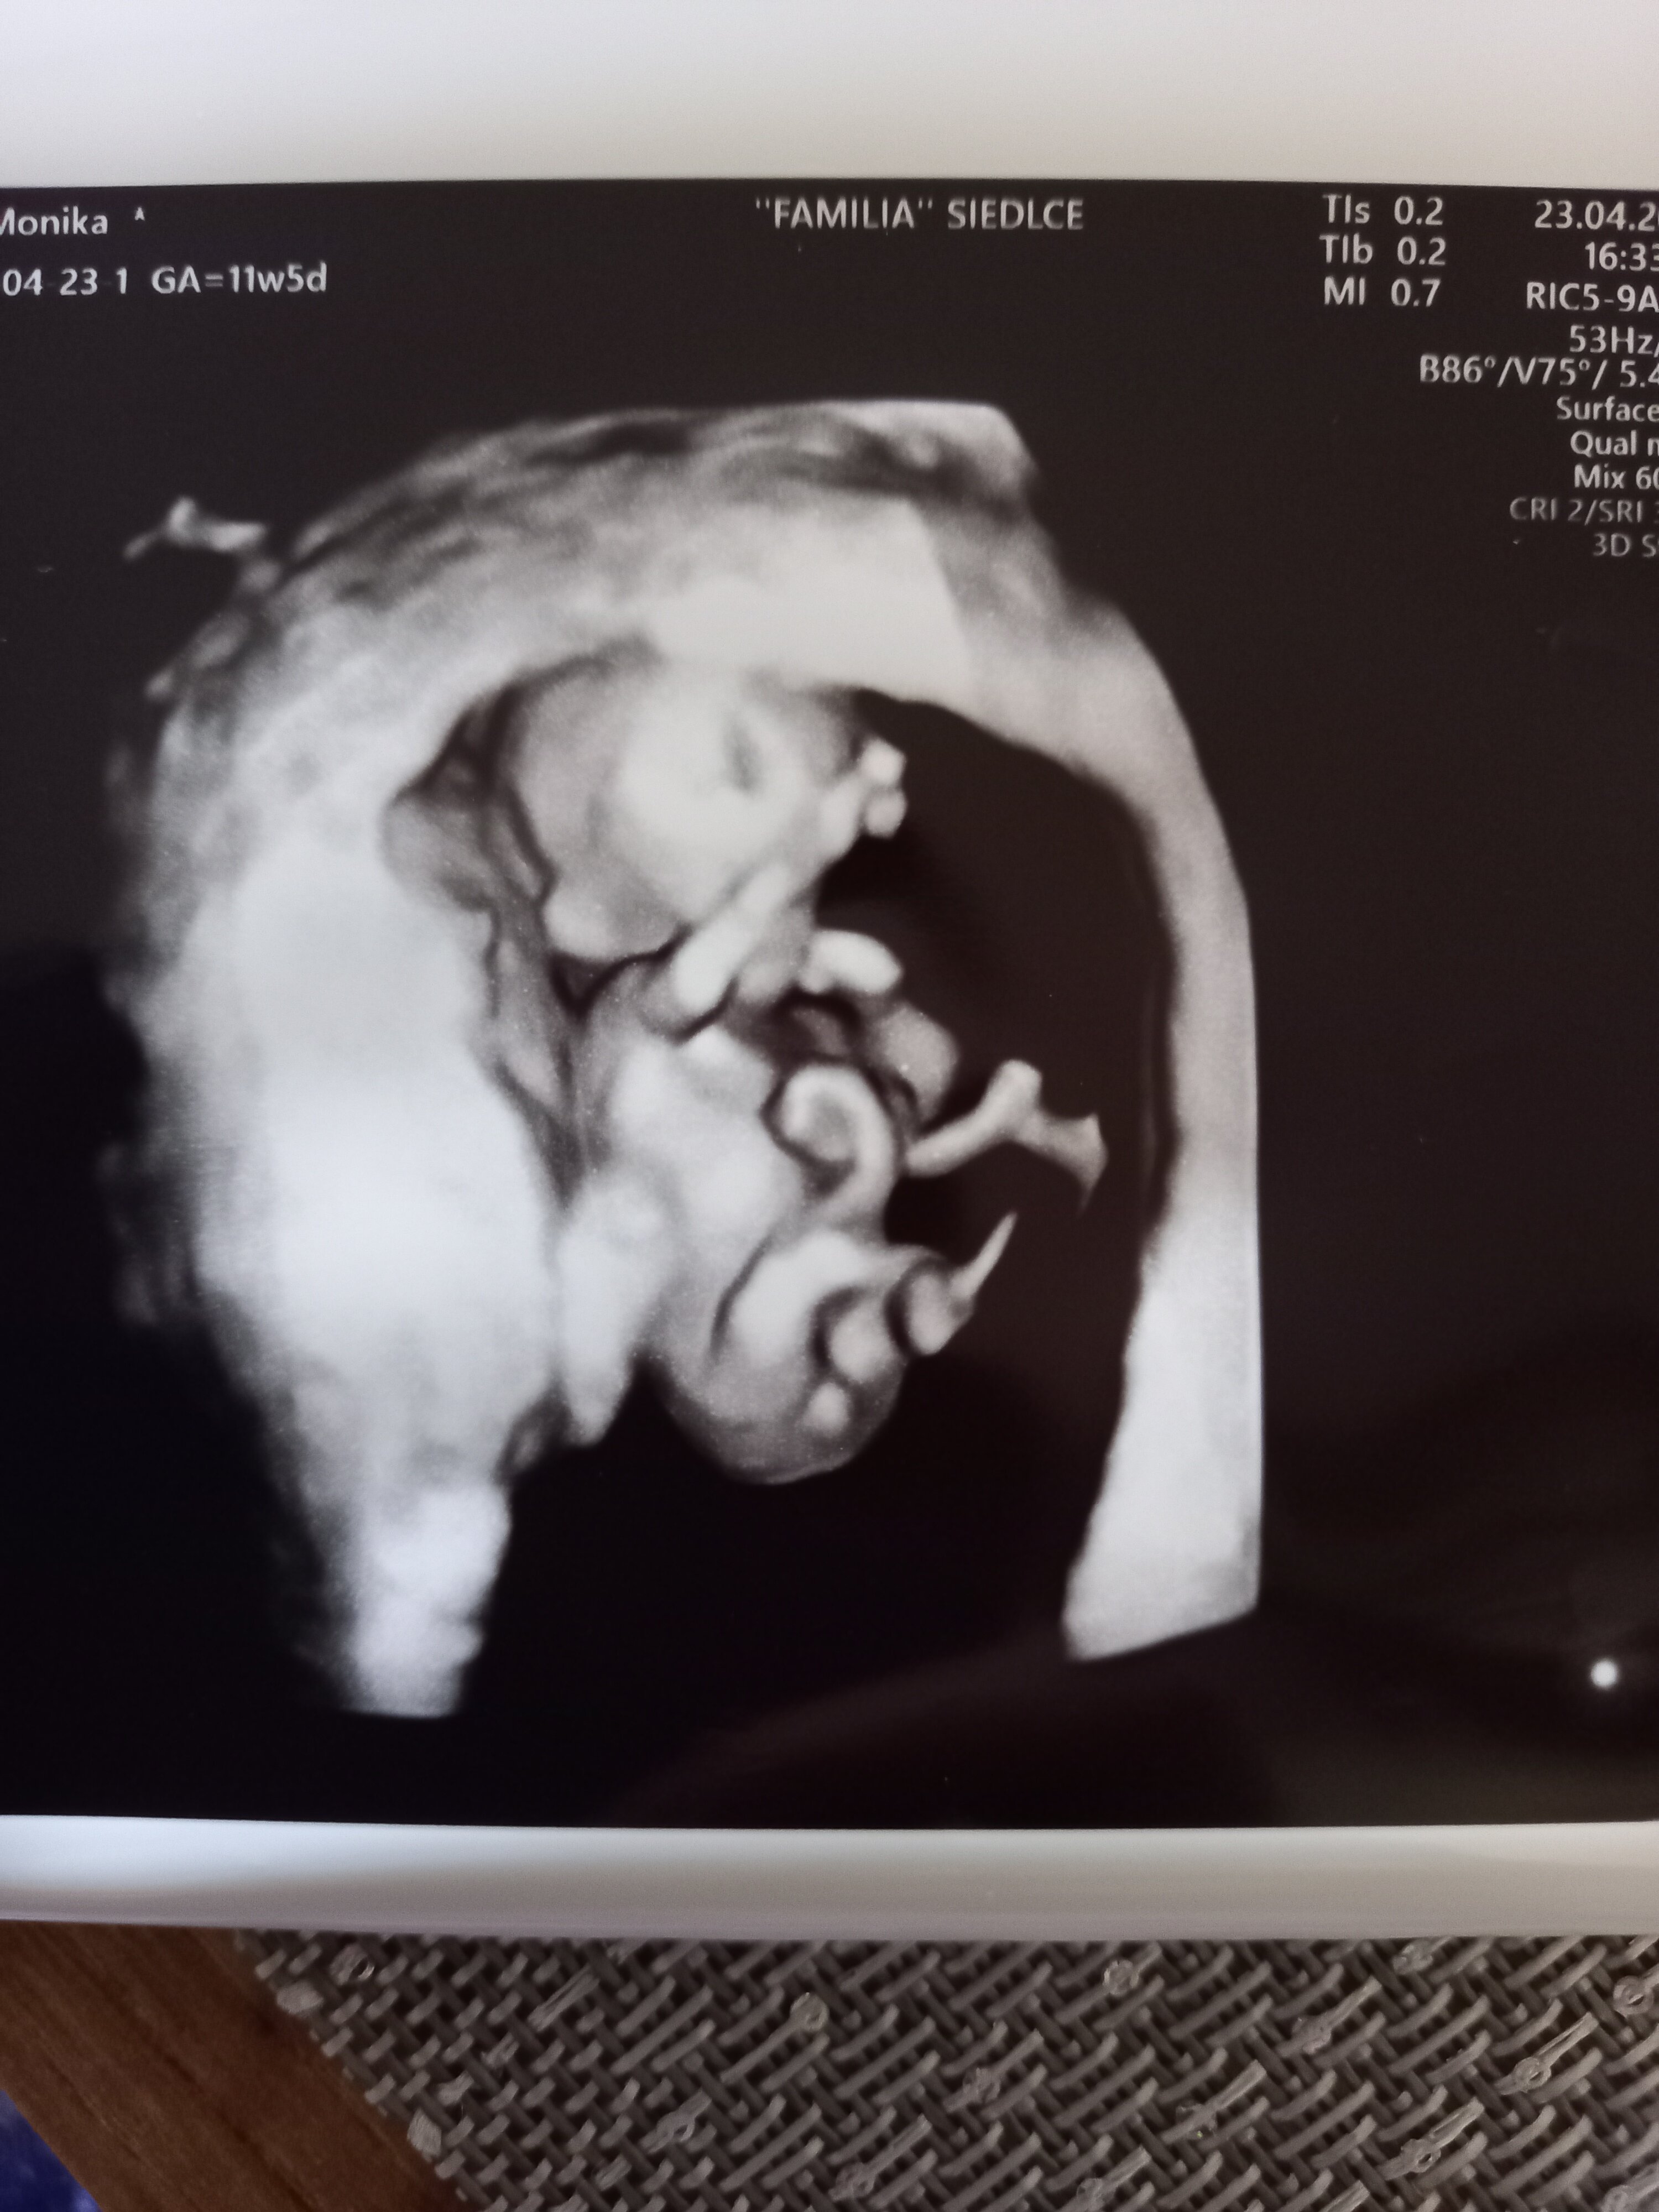

Hej wszystkim . Ja znowu raz na parę dni się pojawiam🤣 zmęczenie robi swoje ale dziś 1 dzien urlopu. Tydzień temu we wtorek miałam usg 1 trymestr i dzidzia miała prawie 6cm. Chciałam wiedzieć czy uda się zobaczyć płeć ale chyba vos tam między nóżkami bylo😂 21 mają się wyjaśni. Co tam u was??? Jakie plany na majówkę??

Moje😍

Załączniki

• 20240426_075003.jpg